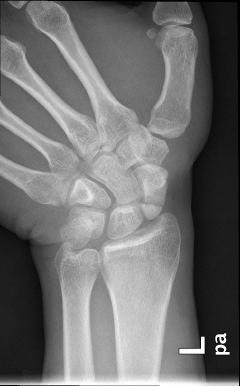

Το σκαφοειδές ανήκει στα μικρά οστά του καρπού και είναι αυτό που υφίσταται κάταγμα συχνότερα. Συνήθως συμβαίνει στις ηλικίες 20 - 40 ετών. Οσο κεντρικότερα (προς τον αγκώνα) είναι το κάταγμα τόσο δυσμενέστερη είναι η πρόγνωση για την πώρωσή του («κόλλημα» του κατάγματος).

Τονίζεται το θέμα της αιμάτωσης του σκαφοειδούς, διότι εύκολα διαταράσσεται σε κατάγματα, με αποτέλεσμα την εμφάνιση επιπλοκών, όπως άσηπτη νέκρωση του κεντρικού τμήματος ή καθυστερημένη πώρωση κσι ψευδάρθρωση (δηλαδή μή πώρωση). Αυτές οι επιλοκές αντιμετωπίζονται χειρουργικώς με χρήση οστικών μοσχευμάτων σε συνδυασμό με σύνθετες τεχνικές (βλ σχετικό κεφάλαιο).